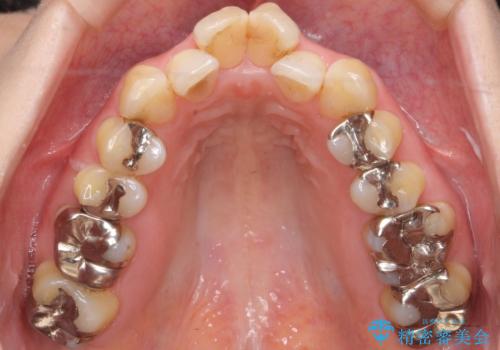

40代の矯正 出っ歯、歯のがたがた

奥歯のかみ合わせのずれと、前歯のがたつきがありました。

上下左右の小臼歯を抜歯しています。

叢生も著しく、少し年齢が上がってからの矯正治療となり、結果ブラックトライアングルが出てしまいましたが、並びの改善で非常に満足していただけました。